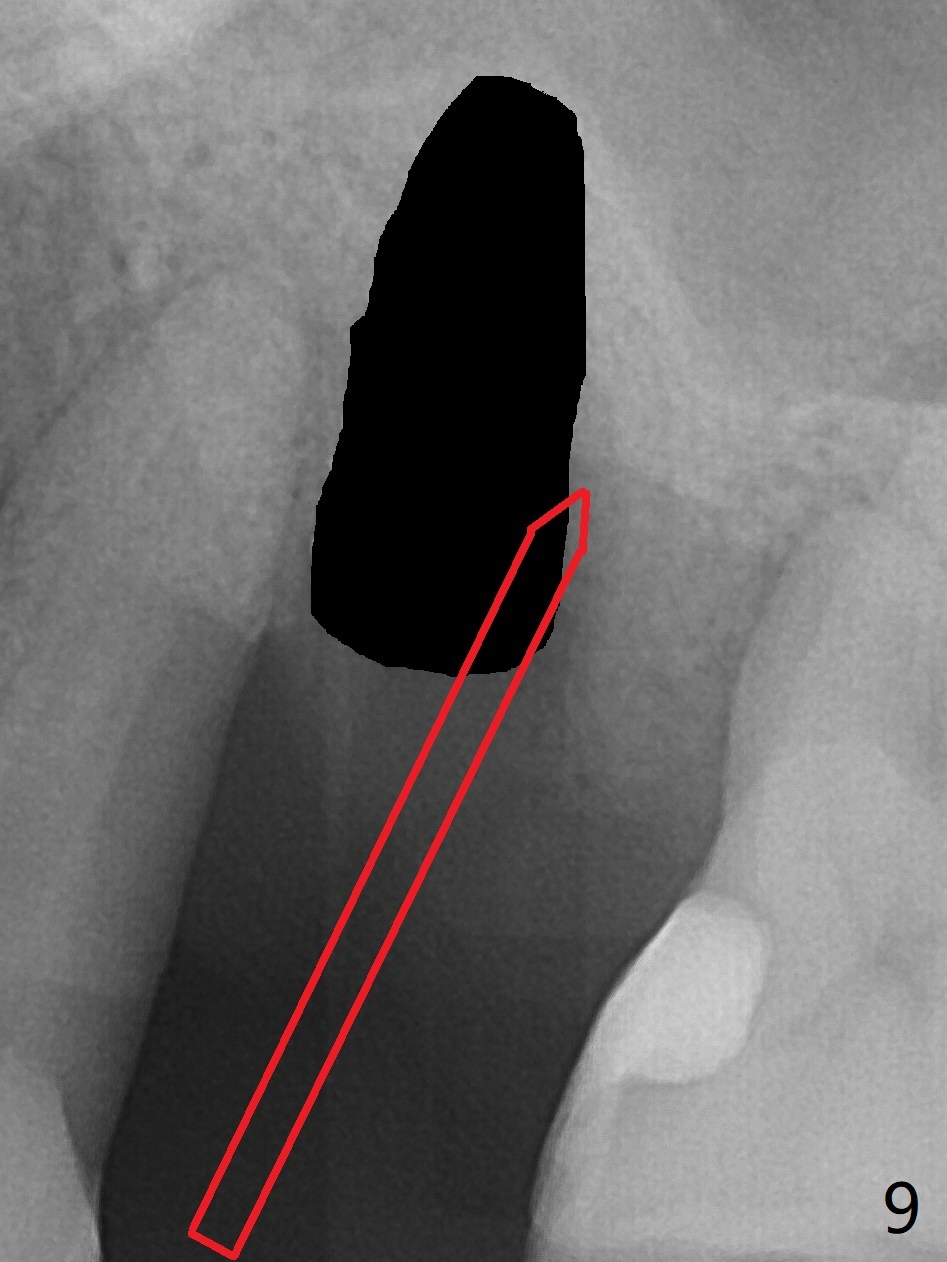

There is more bone apical to the residual root at #13 (Fig.1 red line). An immediate implant along the long axis of the root can be longer, 11.5 mm, favorable for primary stability (Fig.2 (CT taken immediately preop)). The initial trajectory is not ideal (Fig.3). When the pointed/Lindamann bur is removed (Fig.4), effort is made to move the apical end of the osteotomy distal (Fig.5 red arrow) by removing the apical bone (red dashed line). Following sequential osteotomy, a 4x10 mm dummy implant is placed with the trajectory remaining not so ideal (Fig.6,7). As the dummy implant is removed (Fig.8), a new osteotomy is established distal to the existing one (Fig.9). Subsequent drills gradually shift into the original osteotomy (Fig.10 red arrow). When the same dimension dummy implant returns, the trajectory improves with decreased stability (Fig.11). It seems reasonable to place a larger implant without further osteotomy. After placing PRF membrane and Vanilla graft for sinus lift (Fig.13 *), a 4.5x10 mm definitive implant is placed with loss of control in the trajectory (Fig.12,13).

When the initial osteotomy is off substantially (Fig.4), an osteotomy should be established de novo and as early as possible (Fig.14) so that subsequent osteotomy will not relapse to a great extent. More ideally, the initial osteotomy should be planned correctly (Fig.15,16) with sacrifice of the bone height. Nearly 1 month postop, the 4.5x5.5(5) cementation abutment is loose. When it is removed, the patient feels pain from the implant. A 5.5x6 mm healing abutment is placed instead. The implant osteointegrates with trabecular pattern in the sinus 9 months postop (Fig.20 *). The gingiva around the crown at #13 is healthy 1 year 4 months post cementation (Fig.18). Check the distal surface of #13 for bone loss if the tooth #14 is to be extracted.